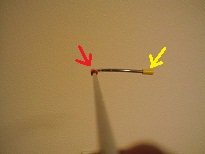

カインズホームで、S字フック98円、ビニールテープ28円X2色で、計154円。

S字フックを切断して、曲げて、ビニールテープを張り付けると、

こんな感じ。

実際には、長いほうの先を目の下に当てて、

赤のテープを見ていて頂いても、黄色も認識できますが、

指の時と同じように、ゆっくりと回すと、

赤を見ていると、黄色が見えなくなります。

大成功です。指でやるときよりも、赤とか黄色とかの指標をしっかりと作る方が、目がきょろきょろしないようです。

150円で作った、この棒。

名前は「栗棒:クリボー」と名付けよう。